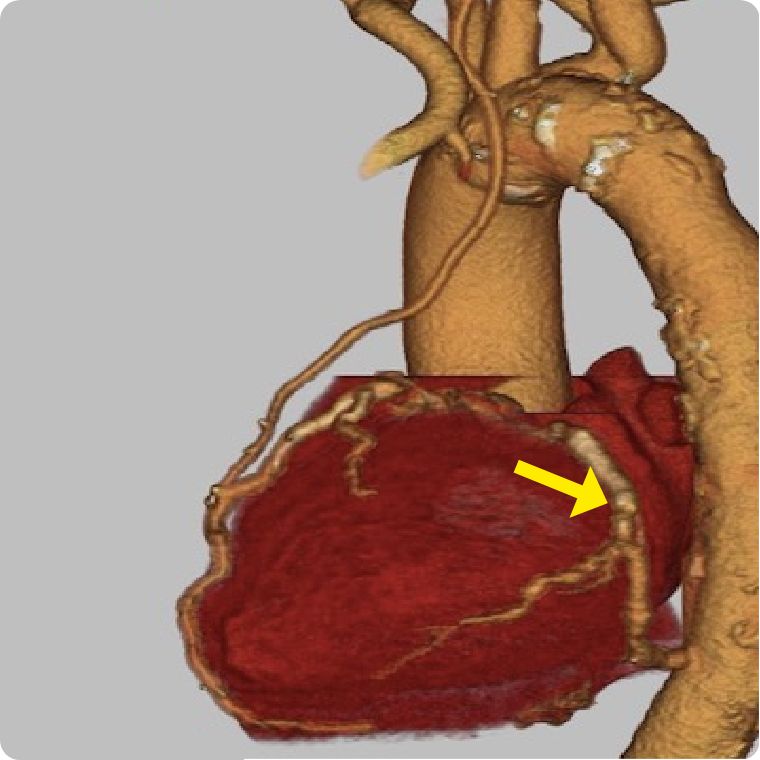

ハイブリッド治療とは本法のMIDCAB (低侵襲直視下冠動脈バイパス術)とカテ―テル治療の長所を組み合わせたものです。

冠動脈バイパス術の長所は、心臓の真ん中を走る一番大事な冠動脈(前下行枝)に内胸動脈をつなげることでカテーテル以上の良好な開存成績が得られる事です。しかし、体の真ん中を大きる切る正中切開法では、体の負担が大きくなってしまいます。一方、ステント治療は静脈を使ったバイパス術とは遜色ない結果であり、体への負担が小さい利点があります。

ハイブリット治療は両者の長所を活かした方法で、高齢者や正中切開が困難な方などには非常に有用な方法と考えております。

循環器内科とのハートチームで患者様の希望に沿った治療を行います。